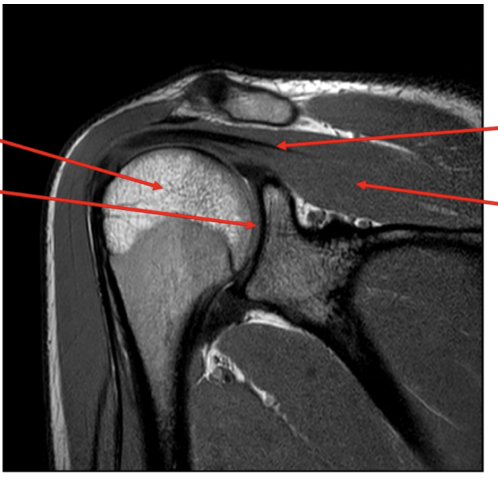

Sequence + pathology?

• PD, PDFS

• Path = supraspinatus tendon tear

• -  You can follow the tendon and see that it stops just above the humeral head rather than

attaching to the lateral aspect of the head.

• -  More prominent of the PDFS you can see high signal around the lateral aspect of the humerus

indicative of a pathological process occurring because of the tear.